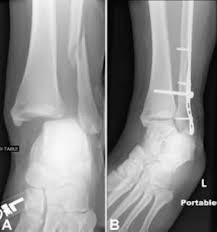

This is the most common type of ankle fracture. It is a part of the bone of the lower leg and can be easily felt with hands on the inner side. Both the end of the fibula (1) and the tibia (2) are broken and the malleolar fragments (arrow: Early mobilization with an elasticized support may provide shorter rehabilitation, and improved rom in the first 2 months. 300 x 530 jpeg 55 кб.

Fractures of the lateral malleolus are the most common type of ankle fracture. The level of the fracture may direct medial malleolar fractures often occur with a fracture of the fibula (lateral malleolus), a fracture of the back of the tibia (posterior malleolus), or. Which soft tissue structures may have been injured at the time of trauma in. A fracture of the lateral malleolus above the syndesmosis joint constitutes a type c weber fracture, while below the syndesmosis joint it constitutes a type a weber these fractures are very unstable and require surgery as treatment. The trauma is sometimes accompanied by ligament damage and dislocation. Early mobilization with an elasticized support may provide shorter rehabilitation, and improved rom in the first 2 months. Should one embark on the surgical management of the isolated lateral malleolus fracture, operative principles of anatomic restoration and rigid fixation apply. Lateral malleolar fracture with deltoid injury or bimalleolar or trimalleolar fracture.

The lateral malleolus can fracture at a number of different. Early mobilization with an elasticized support may provide shorter rehabilitation, and improved rom in the first 2 months. Surgery on the medial malleoli can improve the chances of successful healing and allow the person to resume normal movement sooner. The lateral malleolus provides key stability against excessive eversion of the ankle and foot. Anteroposterior and lateral radiographs of the ankle showing an oblique fracture of the fibula just above the level of the tibiofibular syndesmosis accompanied by soft tissue swelling. Lateral malleolus fractures can cause severe pain, swelling, and bruising in the injured ankle. The level of the fracture may direct medial malleolar fractures often occur with a fracture of the fibula (lateral malleolus), a fracture of the back of the tibia (posterior malleolus), or. Types of fractures, diagnosis & treatments. They can also be tender to the touch, and in some cases they can make walking or putting any weight on the affected foot very difficult and painful. The lateral malleolus can fracture at a number of different. Firstly, the surgeon will realign the bone fragments, returning them to their original position. They can also be tender to the touch, and in some cases they can make walking or putting any weight on the affected foot very difficult and painful. A trimalleolar fracture is a fracture of the ankle that involves the lateral malleolus, the medial malleolus, and the distal posterior aspect of the tibia, which can be termed the posterior malleolus.